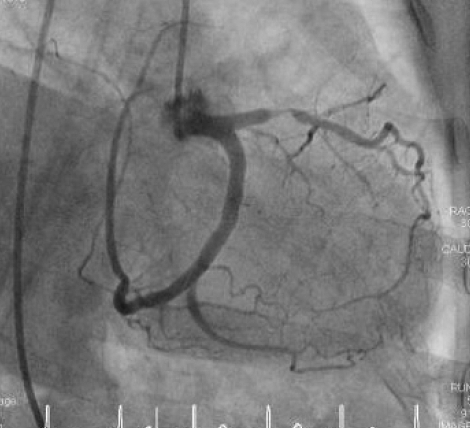

As a routine preparation for a valve replacement, Dr Downes performed an angiogram (or cardiac catheterization), a medical procedure used to determine if there are coronary blockages, which would be addressed also, during the open heart surgery. Neither he nor I really expected to find anything amiss, but we were mistaken…….

February 24: Cardiac Catheterization: A long, thin, flexible tube called a catheter is put into a blood vessel in your arm and threaded to the heart. A special type of dye is inserted in the catheter, which flows through the bloodstream to the heart. Then, Dr Downes took x-rays of the arteries and the heart. This test can show whether plaque has built up inside the coronary arteries, which can narrow or block the arteries and restrict blood flow to your heart.

Dr. Downes found two arteries 90% blocked (Left Anterior descending and Right Coronary Arteries), and one 60% blocked (Oblique Marginal Artery, a branch of the Left Coronary Artery), requiring a triple coronary bypass (Coronary Artery Bypass Graft or CABGx3) which will be performed during the open heart surgery to also replace my aortic heart valve.